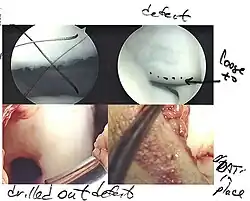

Intact lesions

If non-surgical measures are unsuccessful, drilling may be considered to stimulate healing of the subchondral bone. Arthroscopic drilling may be performed by using an antegrade (from the front) approach from the joint space through the articular cartilage, or by using a retrograde (from behind) approach through the bone outside of the joint to avoid penetration of the articular cartilage. This has proven successful with positive results at one-year follow-up with antegrade drilling in nine out of eleven teenagers with the juvenile form of OCD,[53] and in 18 of 20 skeletally immature people (follow-up of five years) who had failed prior conservative programs.[54]

Hinged lesions

Pins and screws can be used to secure flap (sometimes referred to as hinged) lesions.[55] Bone pegs, metallic pins and screws, and other bioresorbable screws may be used to secure these types of lesions.[56]